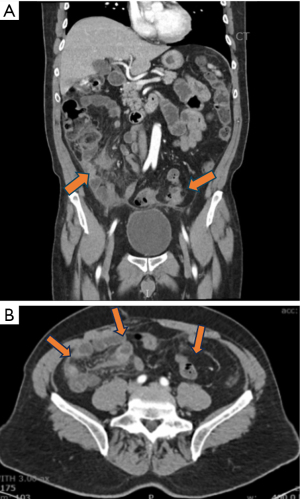

A 62-year-old Caucasian male with a history of diverticulitis was referred to an academic inflammatory bowel disease (IBD) center for reported ileal CD on Humira (adalimumab) 40 mg every 2 weeks. The patient had constant stabbing abdominal pain for 3 years associated with constipation. He had fatigue and early satiety resulting in significant weight loss. He had no history of tobacco use. His mother had colon cancer, but otherwise, there was no family history of malignancy. Although he had reported asbestos exposure for approximately 40 years working as a radio technician, he had no evidence of bilateral pleural plaques or fibrosis. He was diagnosed with ileal CD at an outside hospital based on video capsule endoscopy (VCE) significant for scattered erosions in the ileum. Prior esophagogastroduodenoscopy (EGD) and colonoscopies were unrevealing. He had multiple computed tomography (CT) imaging studies with ileal thickening and moderate inflammatory fat stranding (Figure 1). He did not have iron or B12 deficiency. Fecal calprotectin was not performed. He did not have histologic confirmation of CD. He was given multiple intermittent courses of prednisone by his primary care provider or during emergency room visits. His symptoms of abdominal pain resolved immediately with prednisone. Given his clinical presentation, erosions seen on VCE, ileal inflammation and thickening findings on imaging and improvement on prednisone, he was empirically started on Humira as insurance denied Stelara and Skyrizi. His clinical symptoms did not improve while on Humira.

CT chest revealed no evidence of thoracic metastatic disease. Staging workup at that time revealed no evidence of extra-peritoneal disease. Repeat diagnostic laparoscopy a week later to evaluate for cytoreductive surgery revealed diffuse intraperitoneal disease with majority of small bowel and small bowel mesentery involved with cancer. The patient was deemed a nonsurgical candidate and referred to MD Anderson for opinion regarding further management. Repeat CT imaging one month later showed increasing peritoneal carcinomatosis (Figure 3). The patient was recommended palliative systemic chemo-immunotherapy on protocol 2022-0982 (phase 2 randomized trial of neoadjuvant or palliative chemotherapy with or without immunotherapy for peritoneal mesothelioma) and was randomized to Arm 1 with carboplatin + pemetrexed + bevacizumab + atezolizumab (9).